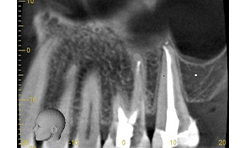

Once the canals are cleaned and shaped to their appropriate size, the root canal system can be obturated. In this case, the tooth was obturated using a warm vertical down pack with Obtura backfill (Figs. 12-15).